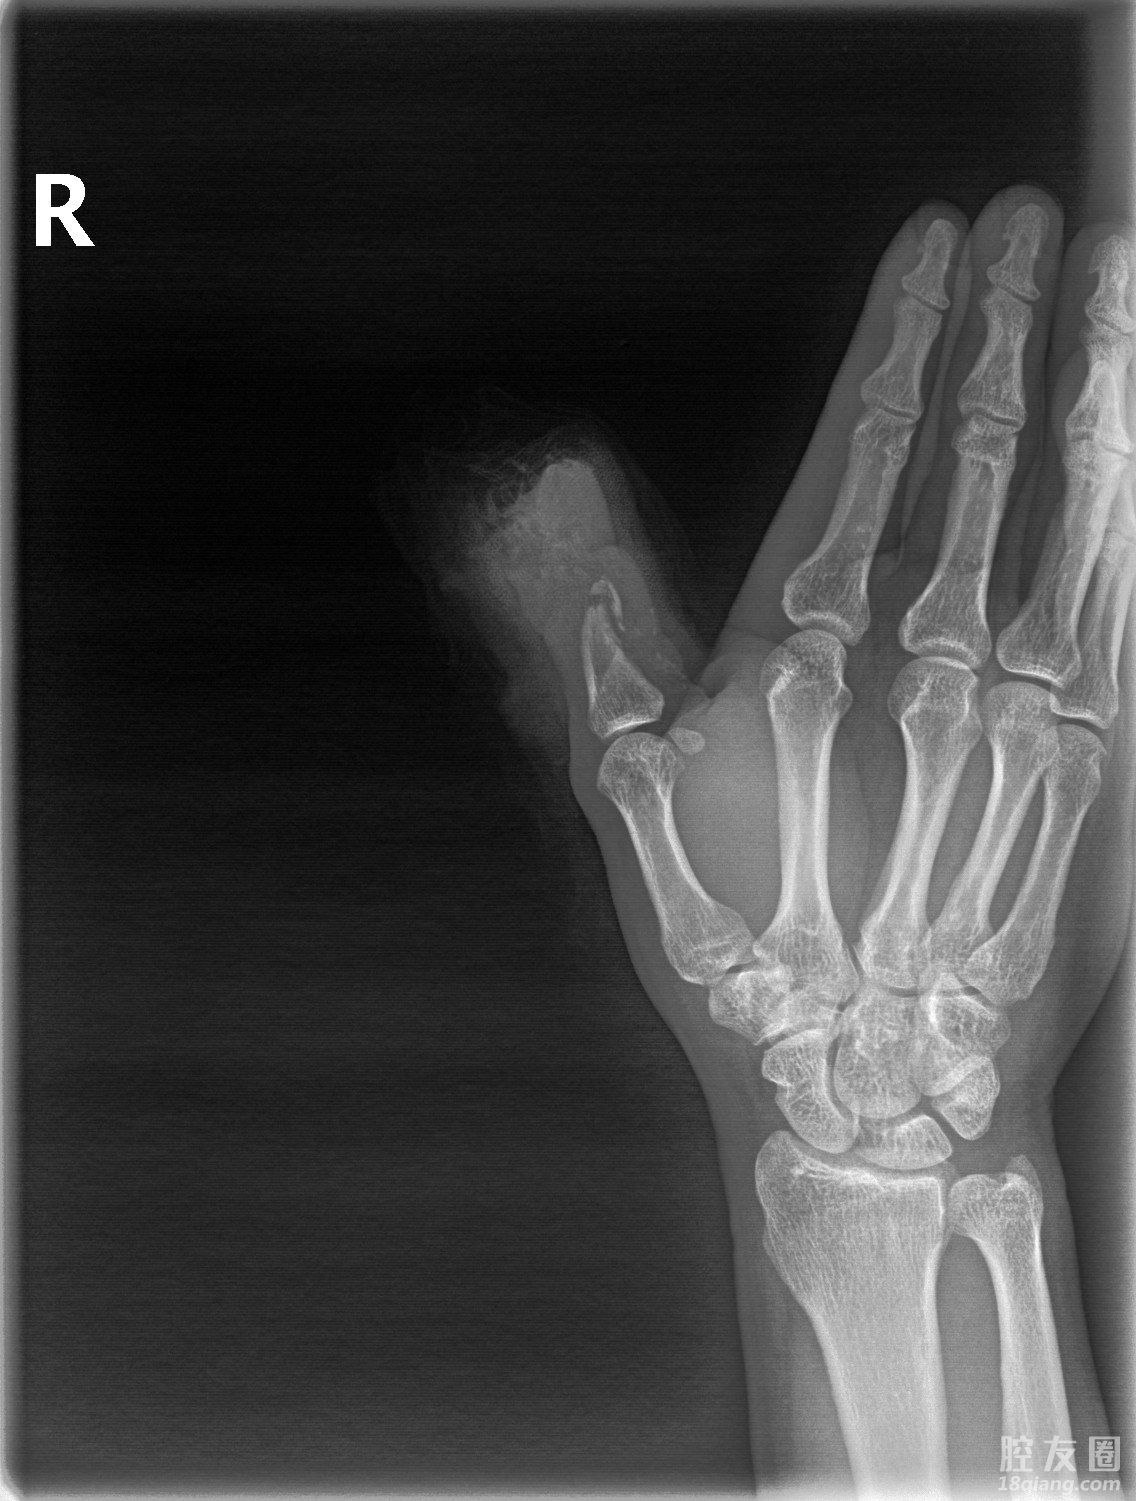

手足外科主任、主任医师杨锦第一时间赶到急诊时候,对老江的伤情进行了详细的评估,发现其右拇指末节离断、出血多、活动受限,近节桡侧至指间关节以远指体缺如,创缘不齐,软组织毁损严重,创面内见较多泥沙污染物,最重要的是离断的手指缺失,已经失去再植的条件。

杨锦介绍,根据老江的情况,团队为其量身定制了分期移植的手术方案,一期手术对右拇指残端进行了细致清创处理;二期手术最为关键,需要根据缺损大小在患者右足踇趾腓侧精准设计带趾骨踇甲瓣进行移植。

手术的关键是显微镜下的精细操作,需要用相当于头发丝三分之一粗细的缝合线进行神经、血管的吻合,每一步都需要精细再精细、严谨再严谨。经过手足外科团队的艰苦奋战,再造的手指外观接近正常手指,血管吻合一次通血成功,血运良好,指体红润、饱满,团队成功完成拇指全形再造手术。